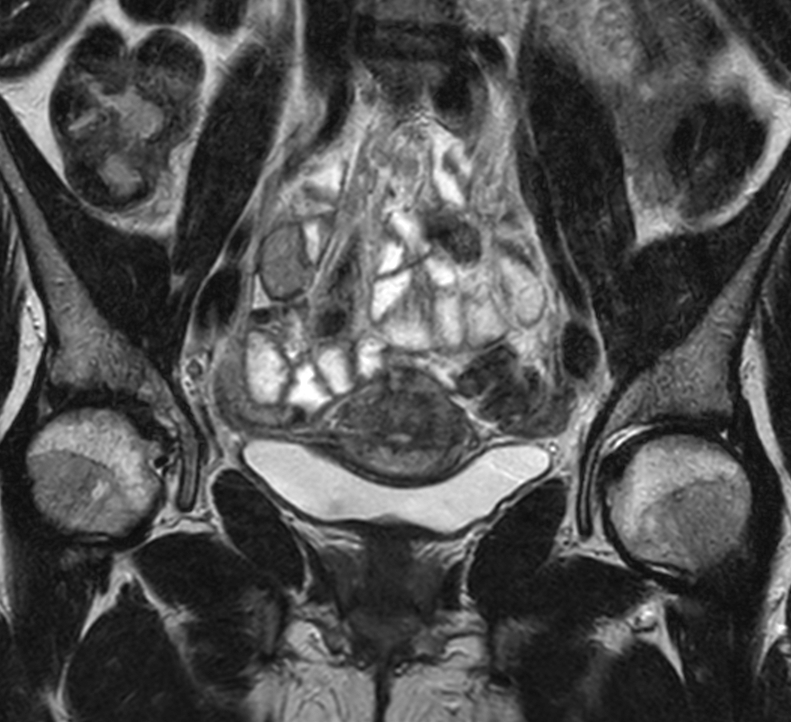

Patient diagnosed with cervical cancer referred for external beam radiotherapy. Three MRIs with different bladder filling were acquired: Half full (mid), empty and full bladder. Patient was imaged at Ingenia MR-RT 1.5T using FlexCoverage Anterior Coil in combination with the integrated Posterior Coil.

Coronal T2w TSE mid